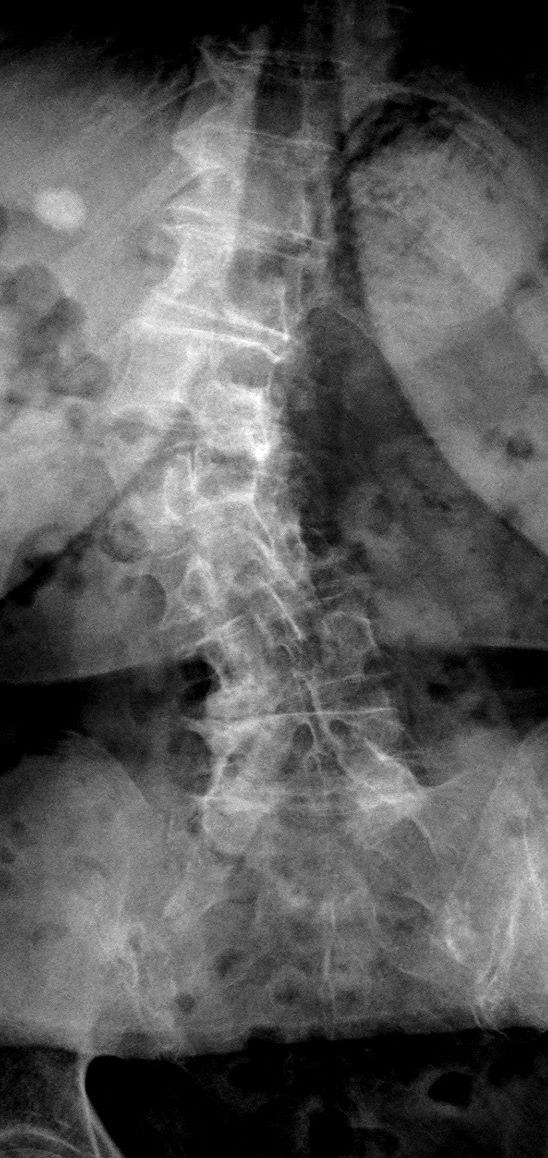

Dopo la laurea e la specializzazione in Neurochirurgia con lode presso il Policlinico Agostino Gemelli, ho dedicato la mia formazione esclusivamente alla cura delle malattie della colonna vertebrale e del midollo spinale, come ernie del disco, stenosi del canale vertebrale, spondilolistesi, metastasi vertebrali e tumori del midollo spinale, attraverso esperienze presso centri di riferimento italiani ed internazionali e a numerosi corsi e master di II livello.

Queste patologie si manifestano con sintomi neurologici (ad esempio: dolore o perdita di forza ad un arto, formicolii, rigidità o perdita di coordinazione alle mani o durante la marcia) oppure con sintomi meccanici (ad esempio: mal di schiena prevalente durante il movimento). Una valutazione specialistica deve mirare a correlare i sintomi clinici con le alterazioni presenti alle immagini radiologiche, ed a guidare il paziente attraverso il percorso di cura, finalizzato al recupero della sua ottimale qualità di vita.

• scoliosi degenerativa dell’adulto;

• cifosi degenerativa dell'adulto;

• deformità degenerative dell'adulto.